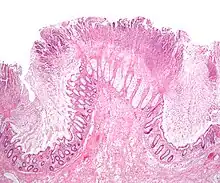

| Pathological specimen showing pseudomembranous colitis | |

The use of systemic antibiotics, including broad-spectrum penicillins/cephalosporins, fluoroquinolones, and clindamycin, causes the normal microbiota of the bowel to be altered. In particular, when the antibiotic kills off other competing bacteria in the intestine, any bacteria remaining will have less competition for space and nutrients. The net effect is to permit more extensive growth than normal of certain bacteria. C. difficile is one such type of bacterium. In addition to proliferating in the bowel, C. difficile also produces toxins. Without either toxin A or toxin B, C. difficile may colonize the gut, but is unlikely to cause pseudomembranous colitis.[45] The colitis associated with severe infection is part of an inflammatory reaction, with the "pseudomembrane" formed by a viscous collection of inflammatory cells, fibrin, and necrotic cells.[20]

Prior to the advent of tests to detect C. difficile toxins, the diagnosis most often was made by colonoscopy or sigmoidoscopy. The appearance of "pseudomembranes" on the mucosa of the colon or rectum is highly suggestive, but not diagnostic of the condition.[46] The pseudomembranes are composed of an exudate made of inflammatory debris, white blood cells. Although colonoscopy and sigmoidoscopy are still employed, now stool testing for the presence of C. difficile toxins is frequently the first-line diagnostic approach. Usually, only two toxins are tested for—toxin A and toxin B—but the organism produces several others. This test is not 100% accurate, with a considerable false-negative rate even with repeat testing.[47]

Pseudomembranous colitis first was described as a complication of C. difficile infection in 1978,[112] when a toxin was isolated from people with pseudomembranous colitis and Koch's postulates were met.